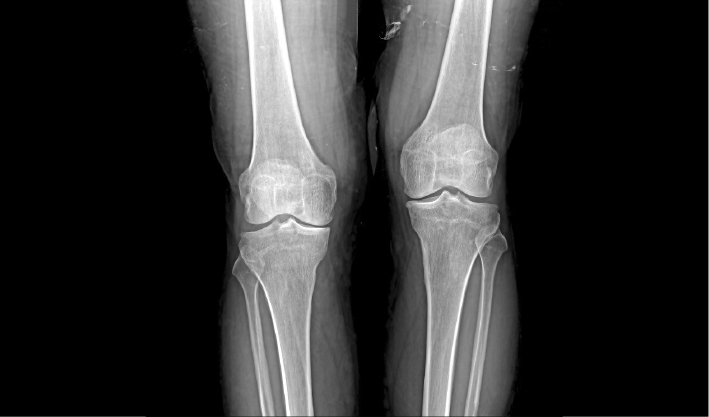

常规DR摄影检查,如:胸片位,腹部位,四肢位等。

成熟优秀的动态成像技术,在透视下实时观察内部器官运动状态,并可快速高清点片,动静结合,多视角精准观察病灶。